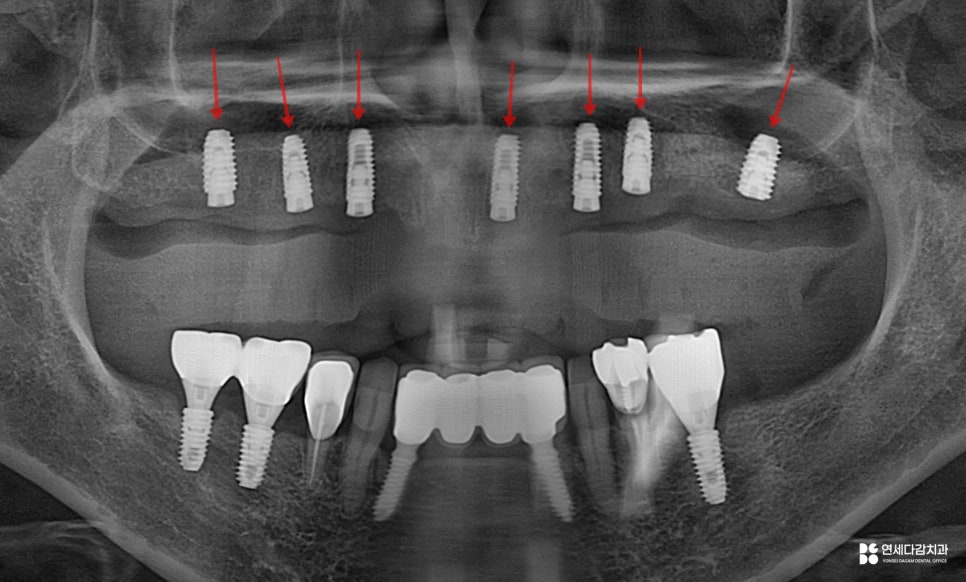

2026.02.04

이처럼 단계적인 과정을 거쳐

가이드를 적절히 사용하면

수술의 정확도를 높일 수 있습니다.

특히 개롱역 치과 에서 설명해 드린 것처럼

뼈 상태가 좋지 않거나 다수 치아가 결손된 분들도

보다 안정적인 수술을 진행할 수 있죠.

이후 뼈와 픽스처가 결합을 마친 뒤

보철을 제작하여 수복하게 되면

기능, 심미성은 모두 회복이 됩니다.